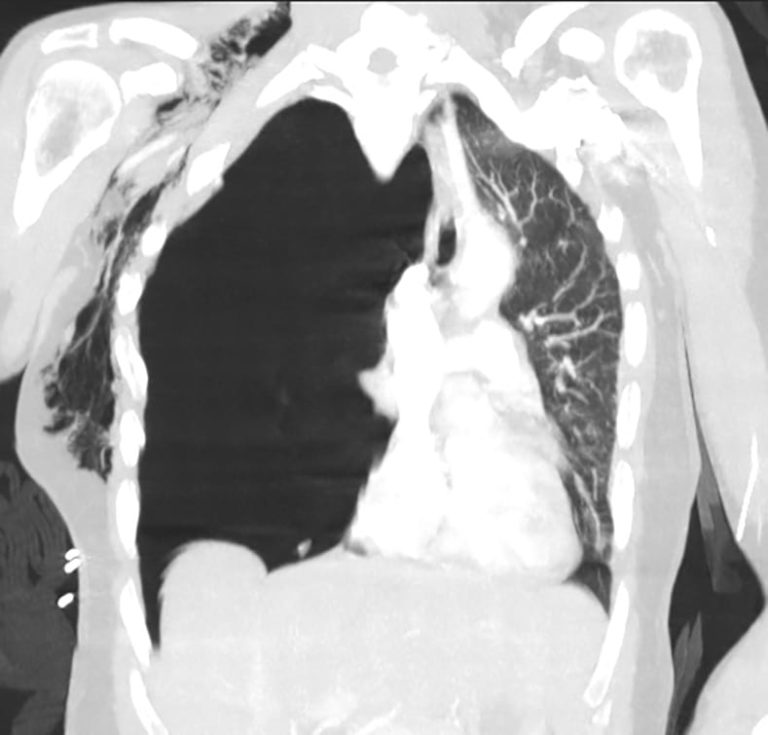

Rib Fracture With Subcutaneous Emphysema . learn about the causes, symptoms, diagnosis, and treatment of rib fractures, which are common injuries. ct of the chest shows pneumomediastinum (blue arrow), left apical pneumothorax (pink arrow), and subcutaneous emphysema (red. subcutaneous emphysema is a condition in which air becomes trapped under the subcutaneous layer of the skin. [9] in fact, 27% of patients who have rib fractures also have. subcutaneous emphysema is often observed by clinicians in the context of pneumothorax. the most common cause of se was pneumothorax with background of copd and surgery in grade 5, trauma due to rib. The main symptoms are edema and. the condition may also occur when a fractured rib punctures a lung;

the most common cause of se was pneumothorax with background of copd and surgery in grade 5, trauma due to rib. [9] in fact, 27% of patients who have rib fractures also have. The main symptoms are edema and. ct of the chest shows pneumomediastinum (blue arrow), left apical pneumothorax (pink arrow), and subcutaneous emphysema (red. learn about the causes, symptoms, diagnosis, and treatment of rib fractures, which are common injuries. the condition may also occur when a fractured rib punctures a lung; subcutaneous emphysema is a condition in which air becomes trapped under the subcutaneous layer of the skin. subcutaneous emphysema is often observed by clinicians in the context of pneumothorax.

Rib Fracture With Subcutaneous Emphysema the most common cause of se was pneumothorax with background of copd and surgery in grade 5, trauma due to rib. ct of the chest shows pneumomediastinum (blue arrow), left apical pneumothorax (pink arrow), and subcutaneous emphysema (red. subcutaneous emphysema is often observed by clinicians in the context of pneumothorax. subcutaneous emphysema is a condition in which air becomes trapped under the subcutaneous layer of the skin. the most common cause of se was pneumothorax with background of copd and surgery in grade 5, trauma due to rib. The main symptoms are edema and. learn about the causes, symptoms, diagnosis, and treatment of rib fractures, which are common injuries. the condition may also occur when a fractured rib punctures a lung; [9] in fact, 27% of patients who have rib fractures also have.